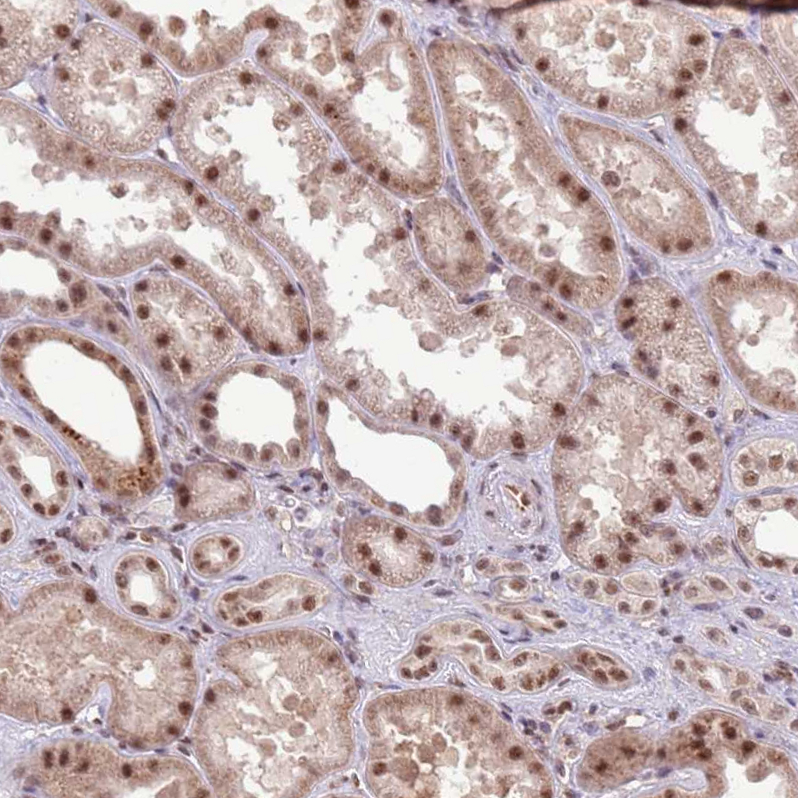

Immunohistochemical staining of human cerebral cortex shows moderate nuclear positivity in neurons.